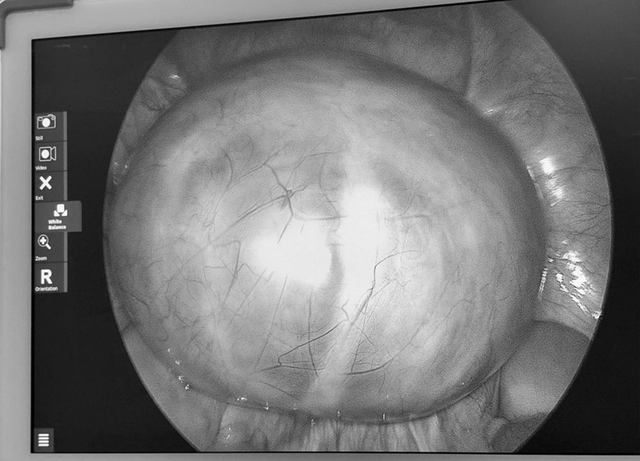

Tại viện qua siêu âm, các bác sĩ phát hiện buồng trứng trái có khối u lớn khoảng 14cm, cấu trúc nhiều vách. Sau hội chẩn, ê-kíp khoa Phụ sản đã tiến hành phẫu thuật vào ngày 3/4. Ca mổ diễn ra thuận lợi, khối u được bóc tách hoàn toàn, đồng thời bảo tồn tối đa chức năng sinh sản cho người bệnh.